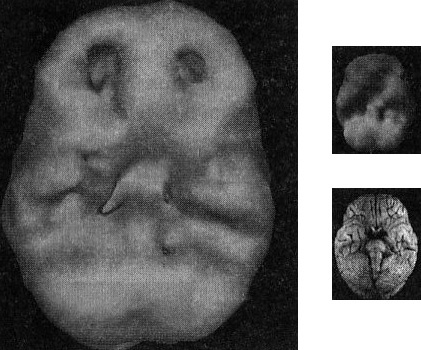

Джилл почти потеряла работу из-за хронических опозданий. Начальник сделал ей последнее предупреждение. На приеме она рассказала, что всегда пытается приходить вовремя, но 7 дней из 10 опаздывает. Проблемы были у Джилл и в школе: учителя жаловались на неустойчивость ее внимания, неорганизованность и слабую работоспособность. Ее томограмма (рис. 2.13) показала низкую активность в коре лобных долей (передняя треть мозга).

Мозг Джилл, страдающей от СДВ (снимок поверхности)

Рис. 2.13 Вид снизу

Обратите внимание на низкую активность передней части мозга Джилл

С помощью правильно подобранного лечения и обучения навыкам тайм-менеджмента Джилл смогла удержаться на работе. Окружающие с готовностью обвиняли Джилл в безалаберности, пока мы не просканировали ее мозг. Улучшив функции своего мозга, Джилл стала более организованной.